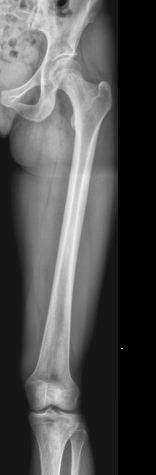

Обследование бедренной кости чаще всего выполняют рентгеновским методом. Это неинвазивный, безболезненный, высокоинформативный и доступный способ получения информации о состоянии и структуре костной ткани. Проходя через тело, рентгеновское излучение больше всего задерживается в самых плотных образования – костных, поэтому на классическом негативном снимке их изображения самые светлые. Патологические изменения, развивающихся здесь, также ясно видны. При их выявлении врач принимает решение о дополнительных видах диагностики и выбирает способы лечения.

• Состояние костной ткани и надкостницы: участки гнойного воспаления, разрежения, размягчения, деструкции, склерозирования, развития опухоли и кистозных образований;

• Изменения в мягких тканях: обызвествление, воспаление, опухоль;

• Целостность кости: свежие переломы, костные мозоли, ложные суставы.В заключении врач описывает преимущественно патологические изменения или пишет, что таких не обнаружено.